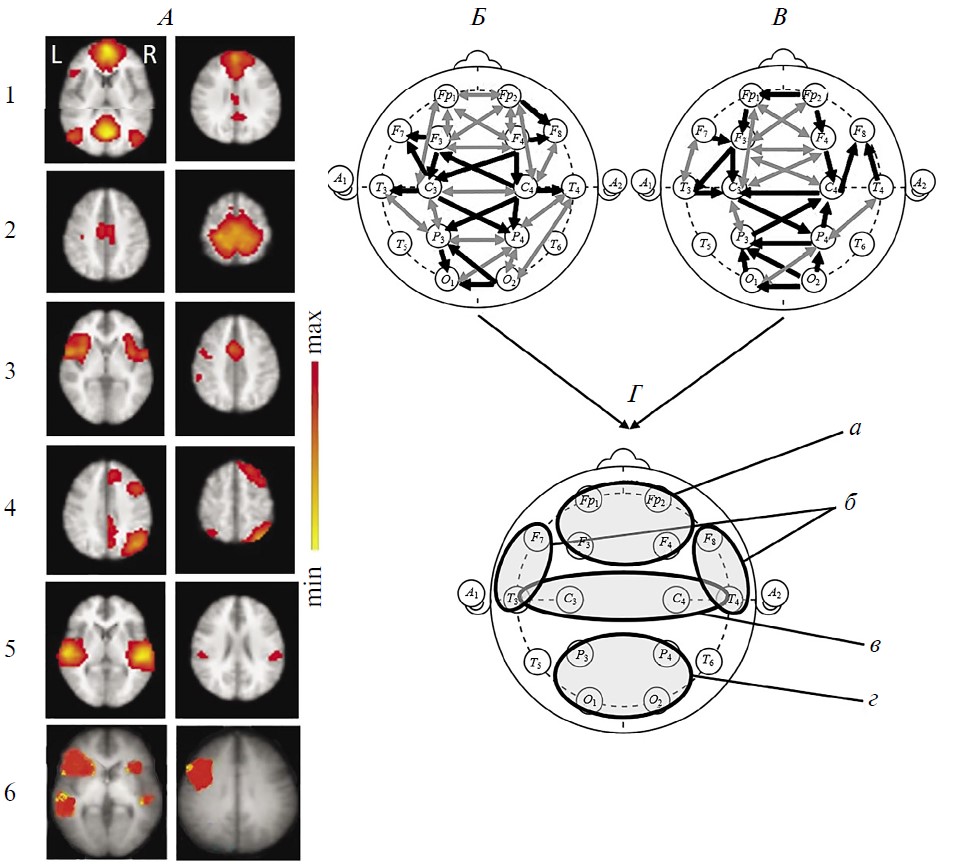

Рис. 4. Динамика сетей покоя функциональной магнитно-резонансной томографии (фМРТ) и коннективности ЭЭГ-диапазона 1–15 Гц в наблюдении 2.

A — исследование 1 (до терапевтической ритмической транскраниальной магнитной стимуляции (рТМС)), состояние акинетического мутизма; Б — исследование 2 (через 17 дней после курсовой рTMС), состояние мутизма с эмоциональными реакциями. I — RSN фМРТ: 1 – DMN, 2 – сенсомоторная, 3 – сеть управляющих функций (исполнительного контроля), 4 – лобно-теменная, 5 – речевая, 6 – слуховая. Шкала справа как на рис. 1. II — коннективность ЭЭГ покоя в непрерывной записи. III — коннективность ЭЭГ покоя в режиме псевдо-ВП. Обозначения линий см. рис. 1 и 2.

Сети фМРТ покоя (рис. 4, I) и до, и после рТМС были представлены только отдельными асимметричными компонентами. До терапии 5 из 6 исследуемых RSN: DMN, сенсомоторной, управляющих функций, лобно-теменной и речевой. За исключением DMN и лобно-теменной, они выражены в левой гемисфере. Наиболее отчетливой была динамика слуховой сети (появление приближенных по конфигурации к норме ее двусторонних компонентов) (рис. 4, Б, I), сопряженной по данным литературы, с активностью лимбической системы [56–58]. Интенсивность большинства RSN имеет тенденцию к снижению после рТМС (рис. 3), за исключением ее нарастания для левой лобно-теменной сети.

Структура коннективности ЭЭГ и при непрерывной записи, и в режиме псевдо-ВП отлична от нормы в обоих исследованиях (рис. 4, II и III). Однако ее изменения более динамичны по сравнению с сетями фМРТ. До рТМС отмечается редукция межполушарных связей, в первую очередь в лобной зоне межсетевого взаимодействия, при сохранности затылочно-теменного локуса. В режиме псевдо-ВП не выражены связи правого височно-передневисочного локуса. Наряду с этим представлены и даже патологически повышены по количеству связи в левом полушарии.

После рТМС коннективность ЭЭГ поменяла свою топологию и латерализацию. Важно отметить появление хотя и ослабленного локуса межполушарных связей в лобных областях при уменьшении активности затылочно-теменного. Инвертировались также внутриполушарные связи: явно увеличились в правом полушарии при их выраженной редукции в левом. Эти изменения отражают формирование также отличного от нормы, но иного по своему содержанию функционального состояния.

Таким образом, менее выразительная (по сравнению с наблюдением 1) позитивная динамика сознания в пределах MCS– в наблюдении 2 сопряжена с активизацией лишь отдельных дополнительных компонентов RSN фМРТ, за исключением появления симметричных составляющих слуховой сети, в сочетании с восстановлением единичных, присущих норме, межполушарных связей ЭЭГ.